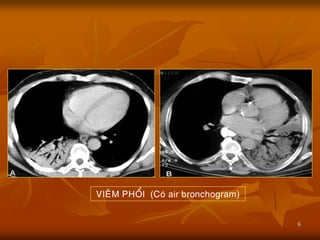

VIEÂM PHOÅI (Coù air bronchogram)

 Giá trị lớn nhất mà dấu hiệu này đem

là, đó là khi có Air bronchogram sign

(+) thì ta có thể khẳng định tổn thƣơng

ở nhu mô phổi, loại trừ tổn thƣơng có

nguồn gốc từ màng phổi, từ thành

ngực, cũng nhƣ từ trung thất.

 Dấu hiệu khí ảnh nội phế quản thƣờng

gặp nhất trong Viêm phổi, nhƣng cũng

có thể gặp trong các bệnh lý khác nhƣ

Phù phổi, Nhồi máu phổi, thậm chí cả

trong bƣớu phổi (bronchioloalveolar

carcinoma, lymphoma).